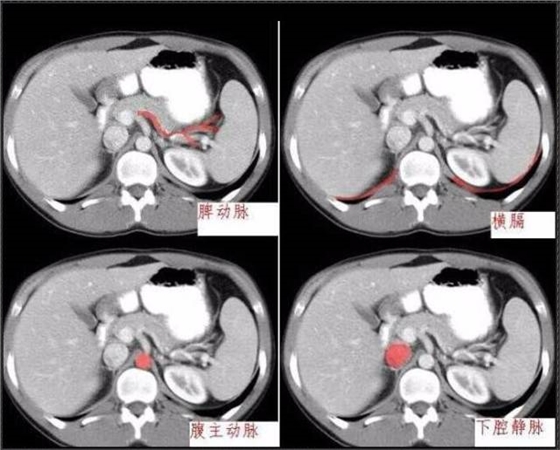

首頁(yè)口腔影像 秒懂:腹部 CT 看這篇就夠

秒懂:腹部 CT 看這篇就夠